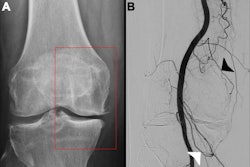

Rossi worked as a full professor and director of radiology at the Sapienza University of Rome. In 1974, he carried out the first angioplasty with a primordial balloon ever conducted in Italy, alongside Dr. Barry Katzen and Dr. Giovanni Simonetti.